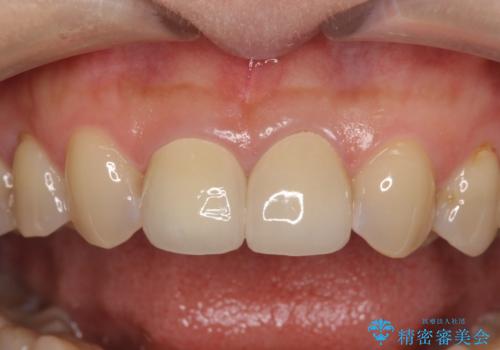

- 上顎2前歯の色を気にして来院された患者様です。

2本ともに虫歯治療による充填材の変色などによりつぎはぎのような前歯となっていたため、オールセラミッククラウンにて補綴治療を行うこととしました。